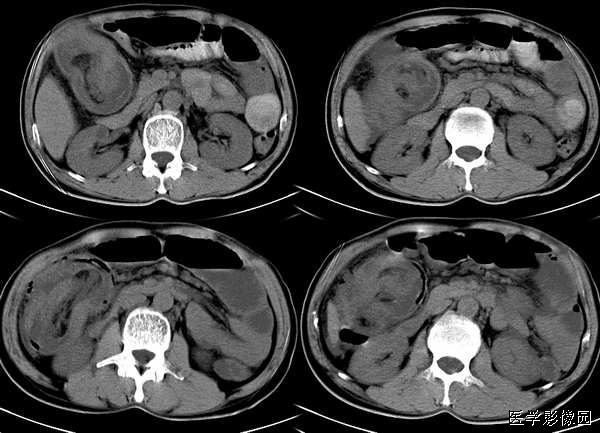

图 1,2 肠系膜脂膜炎。图 1为 MSCT平扫,显示肠系膜密度增高,CT值为 - 47 HU,与腹腔正常脂肪有清楚分界 (箭头) ,且显示肠系膜血管(箭)周围无受累,呈“脂肪环征”。图 2为MSCT门静脉期,显示肠系膜无明显强化,CT值为 - 45 HU,与腹腔脂肪有清楚界限,形成假包膜征 (箭头) ,邻近肠管有推移改变。